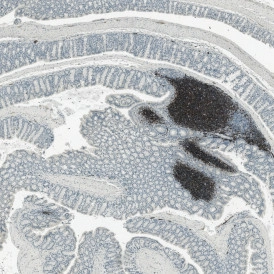

Brightfield slide scanning is a powerful tool in CID research. Utilizing a system like TissueFAXS PLUS can provide whole-slide images of the entire tissue architecture. For example, hematoxylin and eosin (H&E) staining is commonly used to highlight nuclei and cytoplasmic elements. It delivers clear images of cellular morphology and tissue organization. This is essential in identifying pathological changes associated with chronic inflammation, such as cellular infiltration, tissue remodeling, and fibrosis.